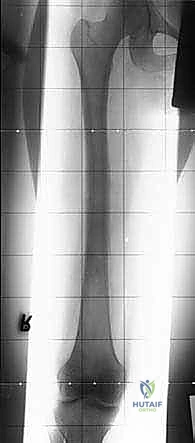

قبل الغوص في التفاصيل المعقدة للعملية الجراحية، من الضروري جداً أن نؤسس فهماً دقيقاً لتشريح عظم الفخذ (Femur). يُعد عظم الفخذ أطول وأقوى وأثقل عظم في الهيكل العظمي للإنسان. إن الفهم العميق لتشريحه، وخاصة مناطق الفخذ القريبة (Proximal - الجزء العلوي القريب من الحوض) والوسطى (Diaphysis - الجذع)، أمر بالغ الأهمية لكل من الجراح والمريض. تُعد هذه المناطق، للأسف، مواقع مفضلة وشائعة لنمو الأورام العظمية الأولية (السرطانات التي تنشأ من خلايا العظم نفسه مثل الساركوما العظمية Osteosarcoma) والأورام النقيلية (Metastatic Tumors - السرطانات التي تنتشر إلى العظم من أعضاء أخرى مثل الثدي، البروستاتا، أو الرئة).

* الساركوما العظمية (Osteosarcoma): الورم الأكثر شيوعاً، يظهر غالباً في منطقة الركبة (أسفل الفخذ أو أعلى القصبة). يتطلب استئصالاً واسعاً مع هوامش آمنة (إزالة جزء من العظم السليم المحيط بالورم لضمان عدم ترك خلايا سرطانية).

* ساركوما إوينغ (Ewing's Sarcoma): يصيب غالباً جذع عظم الفخذ، ويتطلب علاجاً كيميائياً مكثفاً قبل وبعد الاستئصال الجراحي.

| الأشعة السينية (X-rays) | التقييم الأولي السريع لشكل العظم، اكتشاف الكسور المرضية، وتحديد نمط تدمير العظم. | تعطي الجراح فكرة عامة عن حجم المشكلة وموقعها. |

| الرنين المغناطيسي (MRI) | (المعيار الذهبي) يوفر صوراً فائقة الدقة للأنسجة الرخوة، العضلات، الأعصاب، الأوعية الدموية، وامتداد الورم داخل نخاع العظم. | أساسي لتحديد "الهوامش الجراحية الآمنة" ومعرفة ما إذا كان الورم قد مس الأعصاب أو الأوعية. |

| الأشعة المقطعية (CT Scan) | تقييم أدق للقشرة العظمية والتكلسات داخل الورم. كما يُستخدم لتصوير الصدر (CT Chest) للبحث عن انتشار الورم للرئتين. | يساعد في التخطيط ثلاثي الأبعاد لقص العظم وتصميم الطرف الاصطناعي. |